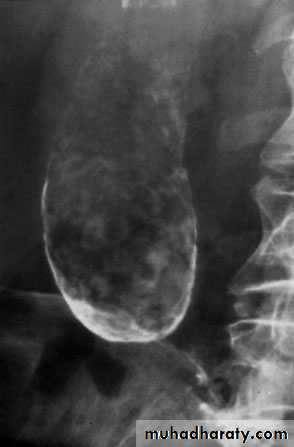

53Transhepatic cholangiogram showing a stricture of thecommon hepatic duct